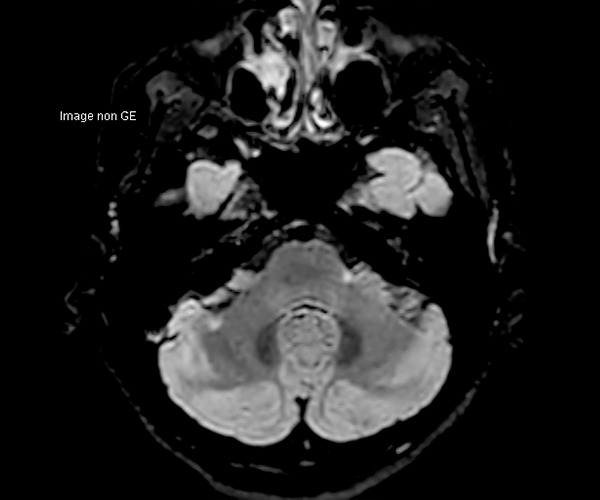

Concernant l’imagerie cérébrale, l’IRM 3T permet d’augmenter la sensibilité de détection de lésions ischémiques aiguës de petite taille, notamment chez les patients adressés pour accident ischémique transitoire (accident vasculaire cérébral), grâce à la séquence de diffusion dont le signal et la résolution sont augmentés.

L’amélioration de la résolution spatiale s’applique à l’exploration morphologique des hippocampes dans le diagnostic de la maladie d’Alzheimer, à la détection de petites lésions de sclérose en plaques ou de métastases, à l’étude fine du cortex dans les épilepsies.

L’augmentation de l’effet de susceptibilité magnétique à plus haut champ permet d’améliorer la détection des hémorragies et est utilisé également dans l’imagerie de perfusion (tumeurs) et l’IRM fonctionnelle (BOLD). L’allongement du T1 à plus haut champ entraîne une meilleure saturation des tissus statiques et par conséquent une augmentation du contraste sang/tissus dans l’AngioIRM.

La séquence de perfusion par marquage des spins artériels (ASL) étudiant la perfusion cérébrale sans injection trouve pleinement son application à 3T dans la pathologie vasculaire, la caractérisation et le suivi post-thérapeutique des lésions tumorales, les démences et certaines pathologies psychiatriques.